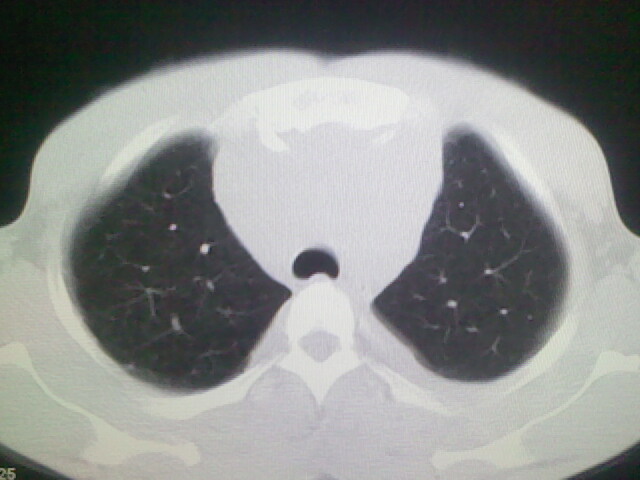

以下是引用杀毒软件在2008-9-3 6:11:00的发言:[br]侵袭性胸腺瘤------一般不侵到气管旁[br][br]考虑----纵隔淋巴瘤,心包及胸膜受累

以下是引用随光逐影在2008-9-3 7:07:00的发言:[br]1)考虑淋巴瘤可能。2)双侧胸腔积液(以左侧为甚)。3)心包积液。